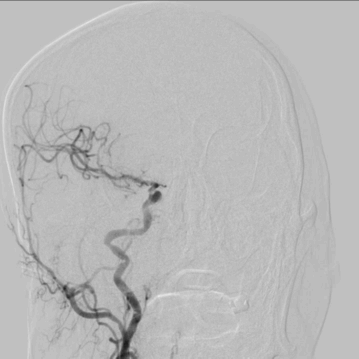

MRA:右侧大脑中动脉闭塞。

脑血管造影:3型主动脉弓,右侧颈内动脉起始段闭塞,后循环及左侧颈内动脉均未向左侧颈内动脉供血区代偿。

3型主动脉弓,用Mani管超选至右颈总动脉,用260cm加硬泥鳅导丝交换出,在泥鳅导丝导引下,用125cm的多功能管将6F Infinity长鞘置于右颈总动脉,提供稳定支撑。

在Synchro2微导丝及微导管引导下,Catalyst7抽吸导管顺利到达颈内动脉末端。

Catalyst 7抽出大量负荷血栓,大脑中动脉上干仍未显影。

微导丝微导管超选至大脑中动脉上干,微导管造影确认在血管内真腔内,释放Solitaire 4×20mm。

Solitaire 4×20mm支架锚定Catalyst 7抽吸导管到达M1段,抽吸导管负压,拉出取栓支架,取栓过程中Catalyst 7维持稳定。

两次支架取栓取栓取出血栓,血管再通。